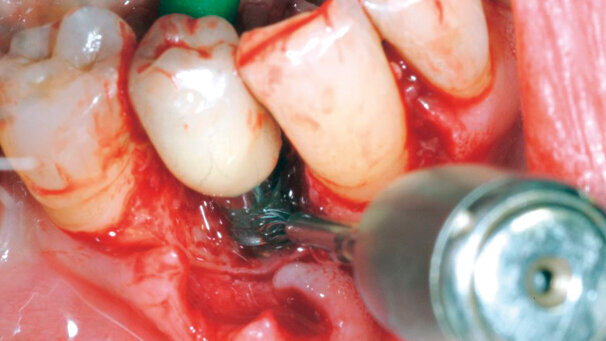

A proposito di complicanze, la più temibile è certamente la perimplantite. Che cos’è? Può illustrarne le caratteristiche?

Premetto subito che il termine etimologicamente non è corretto: la perimplantite è infatti un insieme di complicanze biologiche causa di infiammazione diffusa e perdita di osso attorno agli impianti. Si distingue dalla mucosite, che è altresì un’infiammazione dei tessuti molli attorno agli impianti, ma senza compromissione ossea.